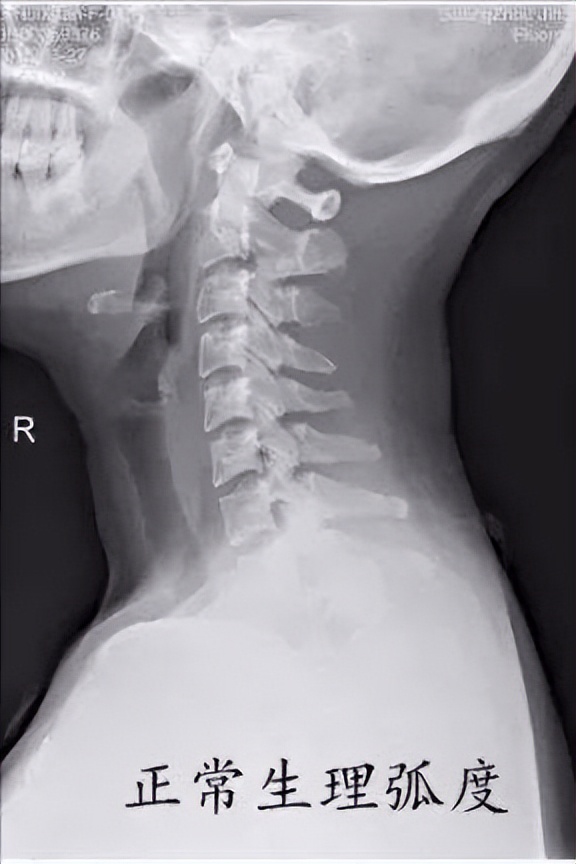

首先我们先来了解我们颈椎正常生理情况。正常的颈椎有一个微微向前的生理弯曲,如下图。它的作用就像个弹簧一样,有效的缓解颈部受到的震荡,而且可以维持姿势的稳定性。